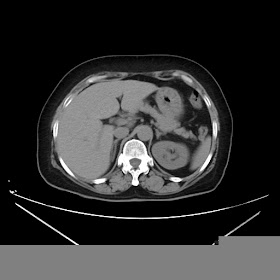

A CT abdomen revealed a left adrenal cortical tumor.

Clinician advised against surgery because she was not in pain. Her TSH is normal. A CT abdomen revealed a left adrenal cortical tumor. Diagnosis of pri. aldosteronism was made. Patient is hypertensive since 1995 since her second childbirth. Now BP is normal with medication. She is nondiabetic. Pt. advised to report her Ca2+ and K+ lvl. monthly. Pt. acq. the habit of eating paan (beetle leaf) from her mother in 2011 when she came to stay with her. Used to eat 3-4 paans a day. Stopped in 2013 after Dr. advised against it.